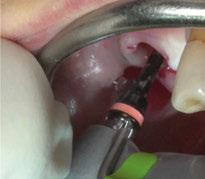

Para ilustrar el proceso, presentamos el caso de una mujer joven diagnosticada de carcinoma adenoide quístico en la región posterior del hemipaladar izquierdo (Figuras 1 y 2). El procedimiento quirúrgico realizado fue una

maxilectomía parcial que incluyó las piezas 24-26 y desde el reborde alveolar hasta la base del cráneo (Figuras 3 y 4). En este caso, la órbita y el globo ocular pudieron ser preservados. La reconstrucción inmediata se realizó mediante un colgajo de músculo temporal homolateral (Figura 5) y el defecto de la fosa temporal fue cubierto mediante una malla de titanio. Posteriormente, la paciente recibió radioterapia (Figuras 6 y 7). 2 años más tarde se diseñó un IS con anclaje en el arbotante nasomaxilar, zona subnasal izquierda

y lo que se pudo preservar del hueso malar. Se añadió una malla sinterizada infraorbitaria para dar volumen a la mejilla y se planificaron dos brazos de conexión que emergieran en las posiciones 24 y 26 de forma subgingival (Figuras 8 y 9). La superficie interna que apoyaba en el hueso era de titanio microrrugoso, y la superficie externa y conectores de titanio pulido y hexágono externo universal (Figuras 10 y 11). La cirugía se hizo bajo anestesia general en infiltración con anestesia local (4% articaína, 1:100.00 epinefrina), levantando el

colgajo cutáneo de la mejilla por vía intraoral, preservando el colgajo temporal para no comunicar con el remanente de la cavidad naso maxilar (Figura 12). Se emplearon 10 tornillos de osteosíntesis de 1,9 mm y la estabilidad primaria obtenida fue excelente (Figura 13)